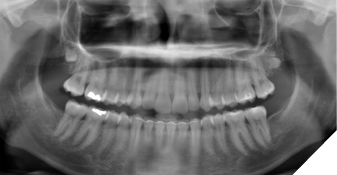

A 15-year-old female was referred for evaluation of impacted third molars. She was asymptomatic with a noncontributory medical history. Clinically, the impacted teeth exhibited completes emergence with no permucosal exposure. Panoramic radiography confirmed impaction of teeth #18, 28, 38 and 48, with suspected early development of a right maxillary supernumerary fourth molar. The maxillary third molars were positioned high in the maxilla, and surgery was deferred to allow further descent of these teeth (Fig. 1).

Fig. 1